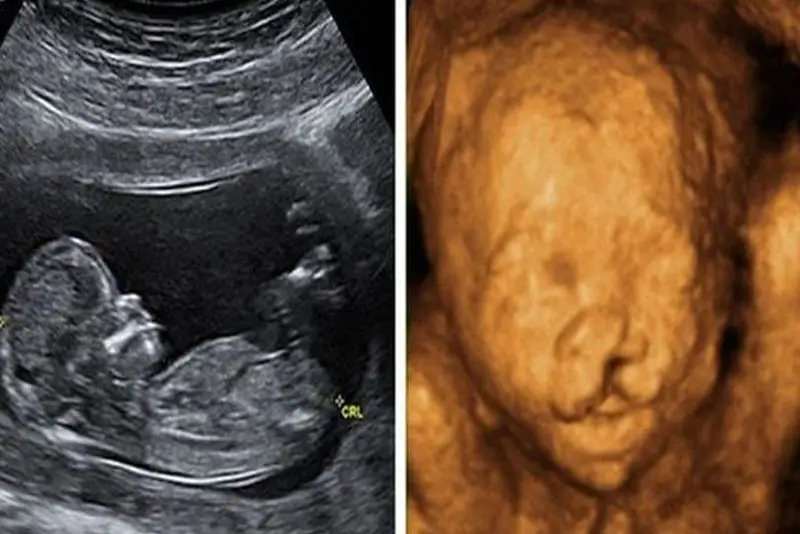

Ở tuần 21 trở đi, bác sĩ siêu âm thực hiện siêu âm hình thái học để kiểm tra cấu trúc chi tiết của thai nhi, bao gồm khuôn mặt, môi, vòm miệng, cũng như các bộ phận khác. Ở giai đoạn này, các bất thường về cấu trúc khuôn mặt, trong đó có hở hàm ếch, thường sẽ được nhận diện rõ ràng.

- Tuần 18–22: Đây là giai đoạn tốt để đánh giá hình thái thai nhi, bao gồm khuôn mặt, môi và vòm miệng. Bác sĩ có thể quan sát các dấu hiệu bất thường rõ hơn. Việc kiểm tra kỹ lưỡng giúp xác định nguy cơ hở hàm ếch chính xác hơn.

- Siêu âm thai: Đây là phương pháp phổ biến và hiệu quả nhất để phát hiện hở hàm ếch. Siêu âm định kỳ giúp theo dõi sự phát triển của thai nhi. Phương pháp này an toàn và không xâm lấn, thích hợp cho tất cả thai phụ.

Siêu âm giúp phát hiện hở hàm ếch ở thai nhi